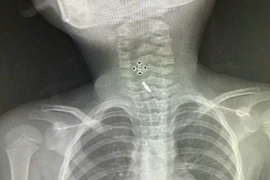

Bệnh viện Sản Nhi tỉnh Phú Thọ vừa cứu thành công một bé gái 5 tuổi bị hóc dị vật kẹp tóc trong thực quản.